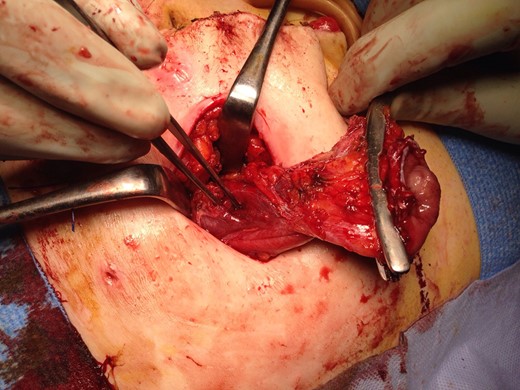

The patient recovered well with the stoma functioning well until Day 6, when she developed a small bowel obstruction. CT scan demonstrated cystic structure compressing the ileum loop within the anterior abdominal loop just before the stoma opening (Figs 1 and 2). Digital stomal examination and Foley’s catheter failed to pass through the stoma opening confirming the obstruction being at the abdominal wall. Failure of supportive measures, the patient was taken to theatre for revision of the stoma. Per stoma endoscopy was attempted with a gastroscope and which also failed to traverse the compression. At surgery, a semicircular skin incision was made adjacent to the stoma revealing what remained of the efferent ileal loop transformed into cystic mass abutting the stoma causing tight compression and was tightly adherent to the afferent ileal loop (Fig. 3). This was drained and partially excised with limited mobilization of the stoma. The remnant mucosa adherent to the afferent ileal loop was cauterized. Her recovery was unremarkable and was discharged Day 4 postsurgery. Histopathology of the partially excised cyst wall confirmed small bowel with viable mucosa showing mucosal flattening and complete loss of the villi.

Cross sectional CT Image showing compression of ileostomy opening.